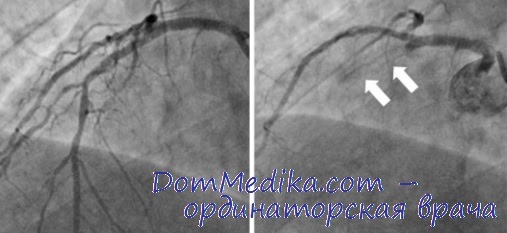

Хроническая окклюзия артерий: причины, симптомы и лечение